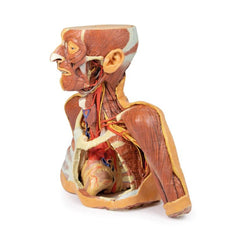

3D Printed Sagittal Section of Head with Infratemporal Fossa Dissection

3D Printed Sagittal Section of Head with Infratemporal Fossa Dissection

This 3D model provides a combined midsagittal section through the head and

superior neck coupled with a deep dissection into the infratemporal fossa

region and superficial dissection of the scalp.

On the opposing side of the model, a superficial and deep dissection has

opened a large window into the anatomy of the lateral scalp and infratemporal

fossa. Across the scalp there is a well preserved posterior auricular nerve

and superficial temporal artery highlighted on the superficial surface of the

temporalis muscle. Anteriorly, the temporalis has been dissected to expose

the deep temporal arteries arising from across the maxillary artery.